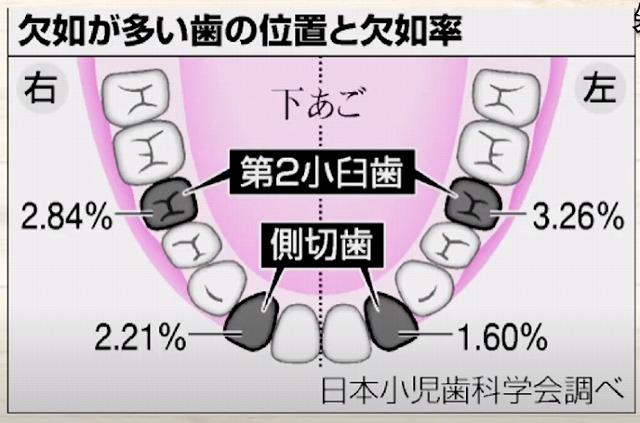

特に前方から数えて

2番目の歯と

5番目の歯が

足りない方が多いです。